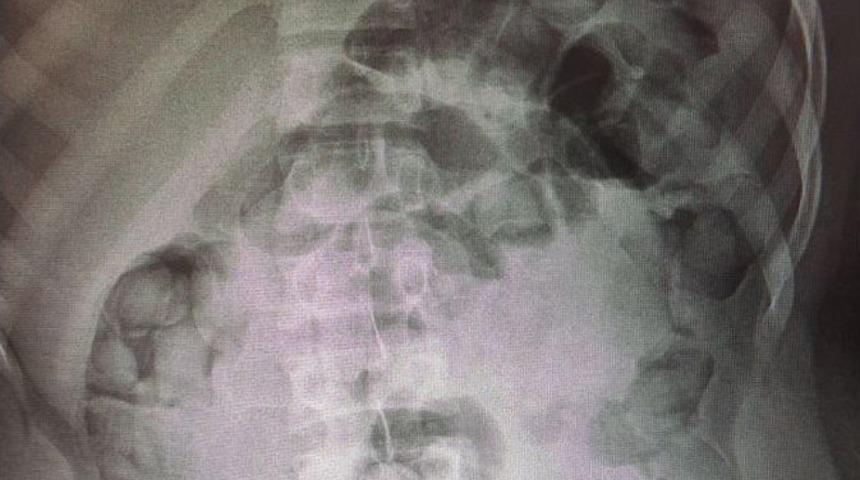

Elazığ’da İranlı uyuşturucu kuryesinin midesinden 97 adet kapsül içinde 1 kilo 235 gram ham eroin maddesi çıktı.Edinilen bilgiye göre, Elazığ ve Van Emniyet Müdürlüğü Narkotik Suçlarla Mücadele Şube Müdürlüğü ekipleri, uyuşturucu tacirlerine yönelik ortak çalışma yaptı. Polisin yaptığı çalışmada Elazığ-Bingöl yolu üzerinden durdurulan bir otobüste arama yapıldı. Yapılan aramada İran uyruklu Khoshkar Hıva (28) sahte pasaportla yakalandı. Yakalan şüphelinin midesinde uyuşturucu madde olabileceği değerlendirilmesi üzerine hastaneye götürülerek iç beden muayenesi yapıldı. Muayenede röntgeni çekilen şüphelinin midesinde uyuşturucu madde olduğu tespit edildi.97 adet kapsül şekilde yutarak mideye saklanan 1 kilo 235 gram ham eroin maddesi doktor kontrolünde çıkarıldı. Uyuşturucu maddeye incelenmek üzere el konulurken şüpheli ifadesi alınmak üzere İl Emniyet Müdürlüğü’ne götürüldü.Midesinde eroin çıkan ve sahte pasaportla yakalanan şüphelinin "Uyuşturucu Madde Ticareti Yapmak" suçundan adliyeye sevk edilmesi bekleniyor.Olayla ilgili soruşturma sürüyor.